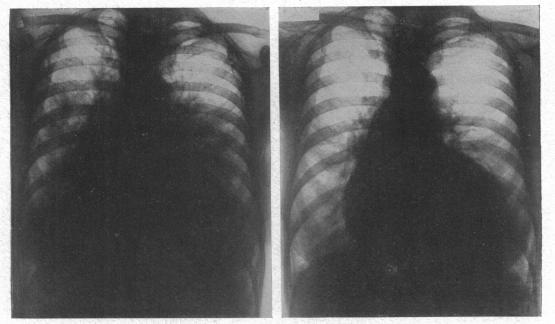

The radiology of acute pulmonary oedema.

Br Heart J. 1951 Oct;13(4):503-18. doi: 10.1136/hrt.13.4.503.